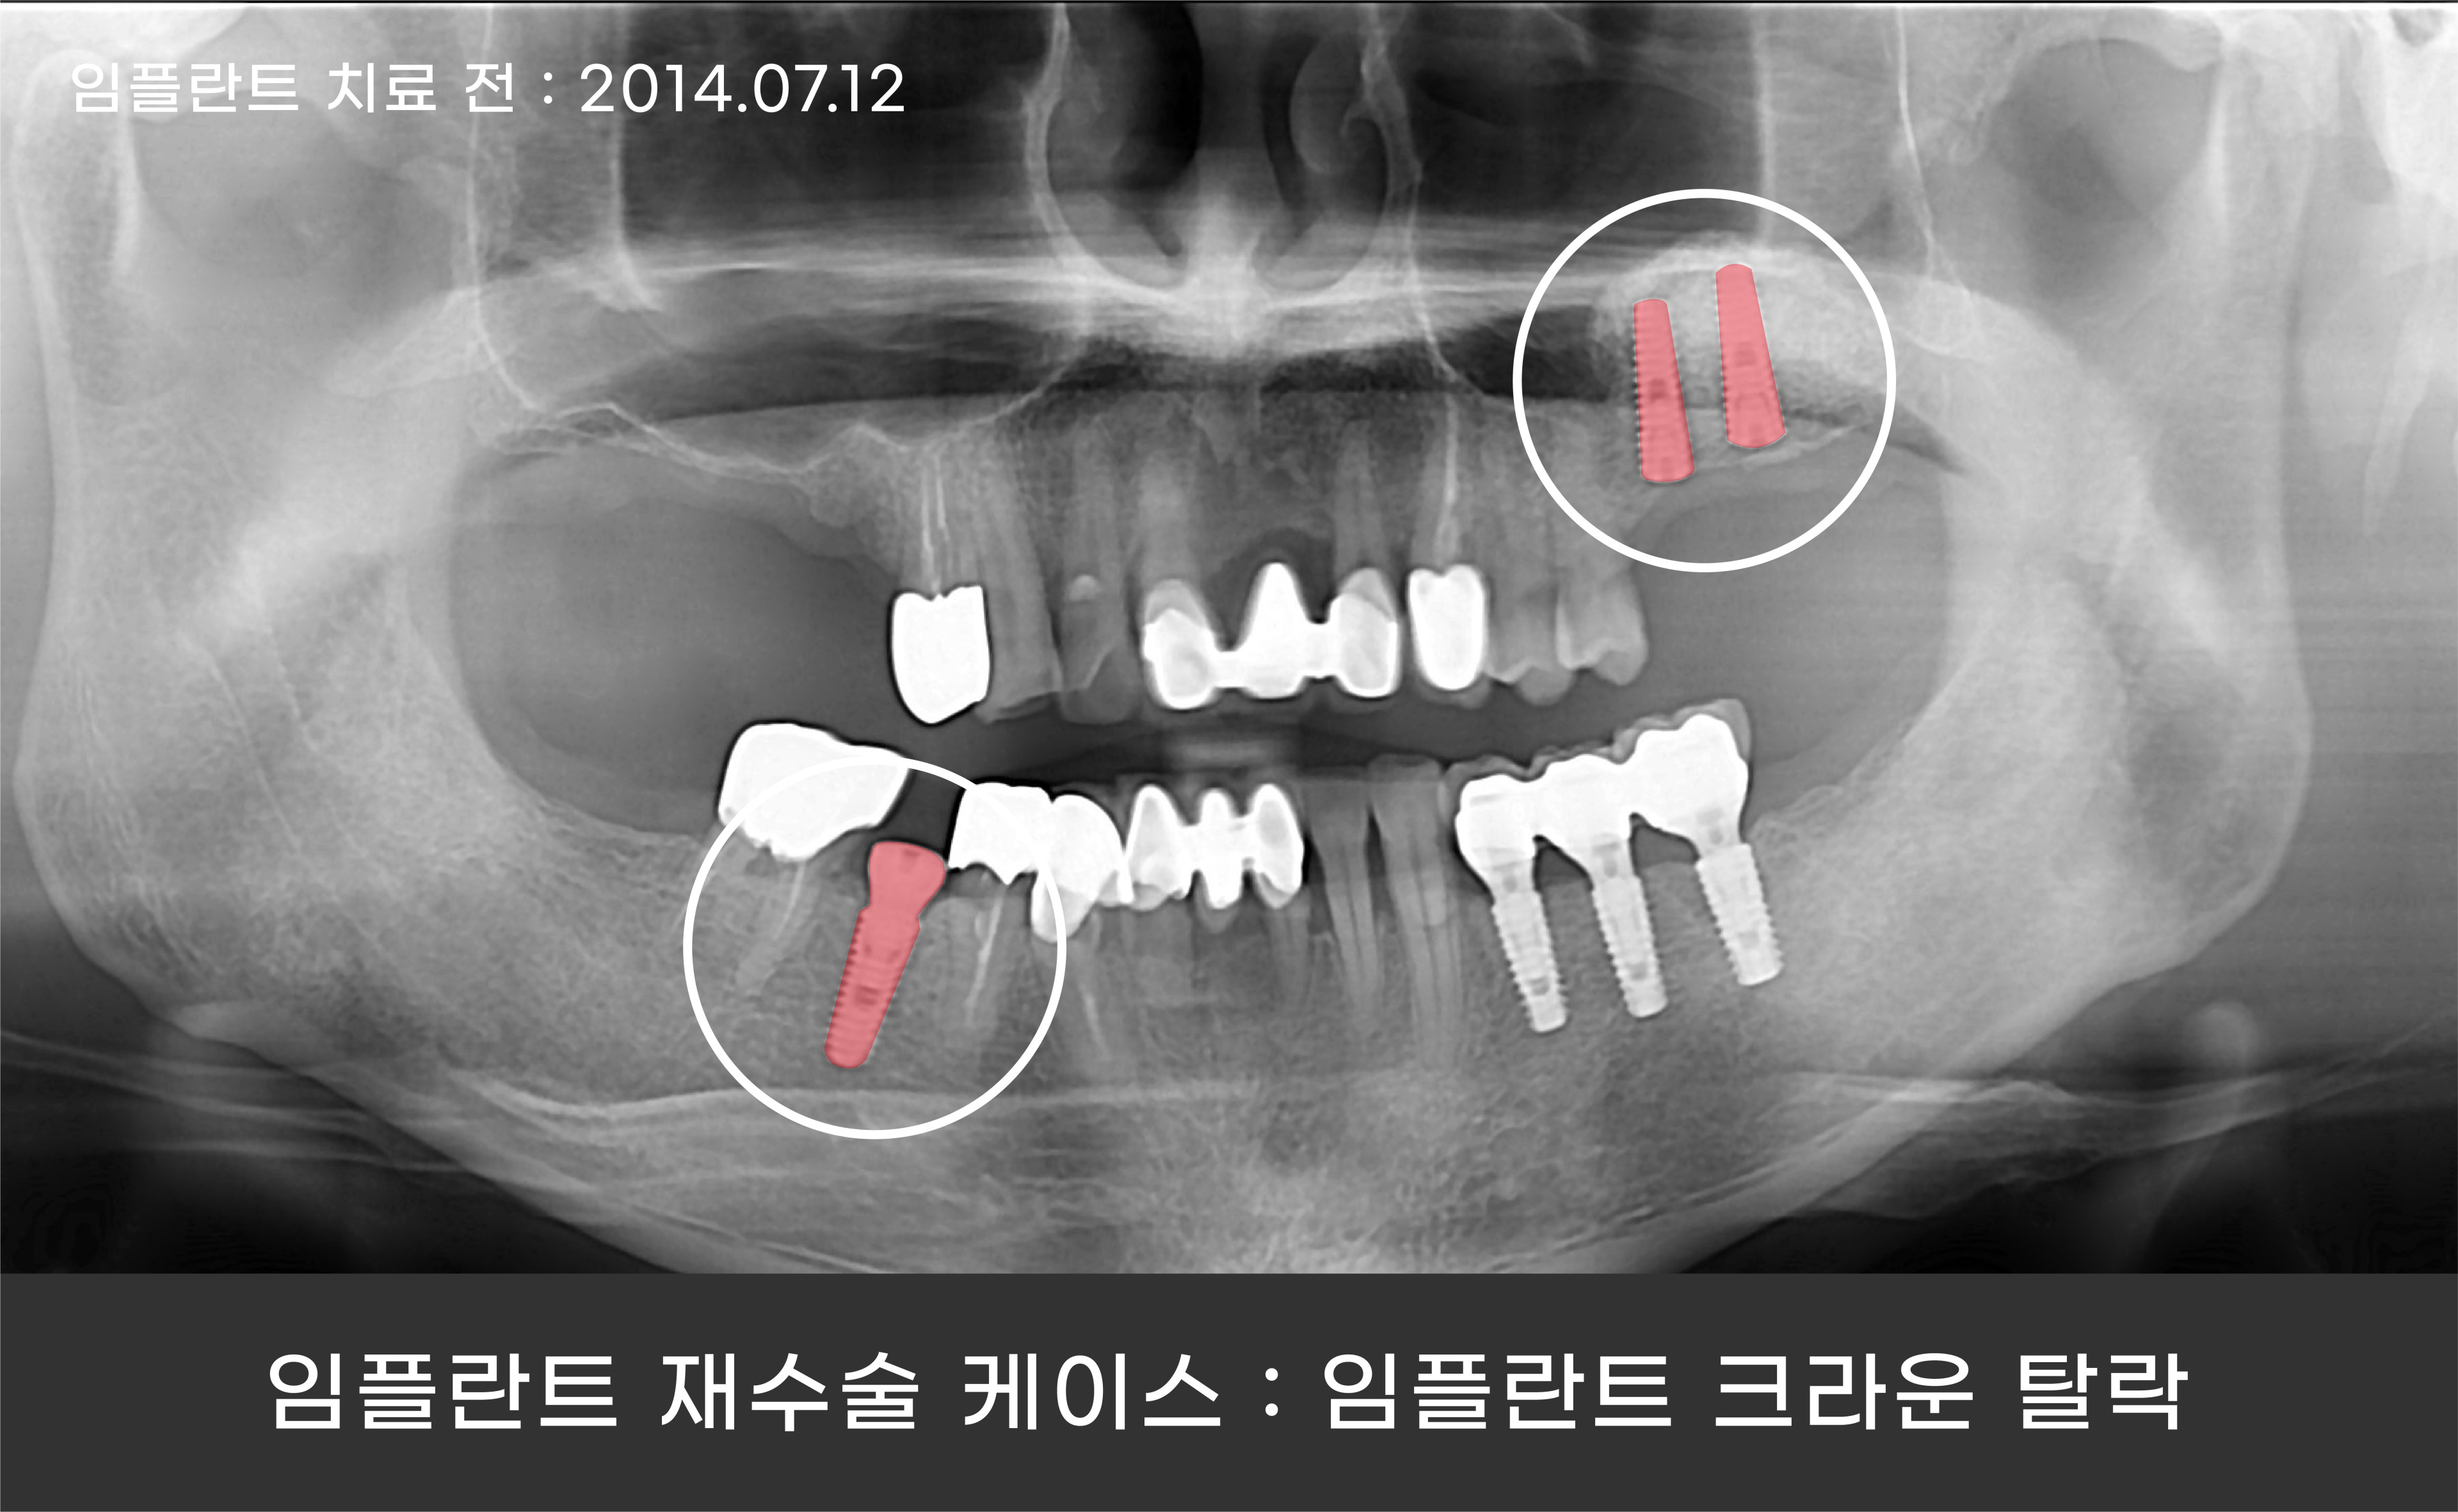

10년 전 임플란트 재수술 케이스를 통해 함께 보시겠습니다!

환자분의 경우에는 임플란트 크라운의 탈락으로 내원해 주셨는데요.

임플란트 크라운이 손상되는 대부분의 원인은 질기고 단단한 음식을 자주 섭취하거나

이 악무는 습관, 이갈이 등 임플란트에 가해지는 충격이 누적되면서 크라운이 깨지거나

빠지게 됩니다.

이러한 습관은 임플란트 보철에 좋지 않은 영향을 끼칩니다.